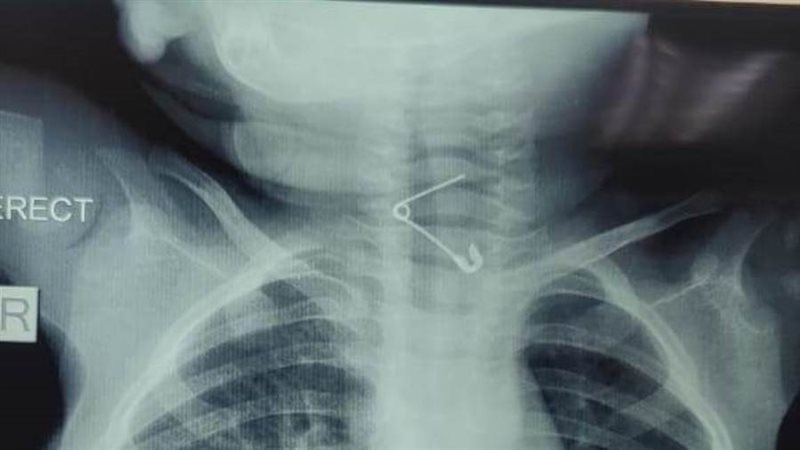

عمره عام.. إنقاذ حياة رضيع ابتلع "دبوس" بمستشفى الأطفال التخصصي ببنها

نجح فريق طبي بقسم جراحة الأطفال بمستشفى الأطفال التخصصى ببنها في محافظة القليوبية، في إنقاذ حياة طفل بلغ من العمر عامًا، ابتلع دبوسًا معدنيًا استقر في الحلق، مهددًا مسار التنفس ومسببًا خطورة بالغة على حياته.